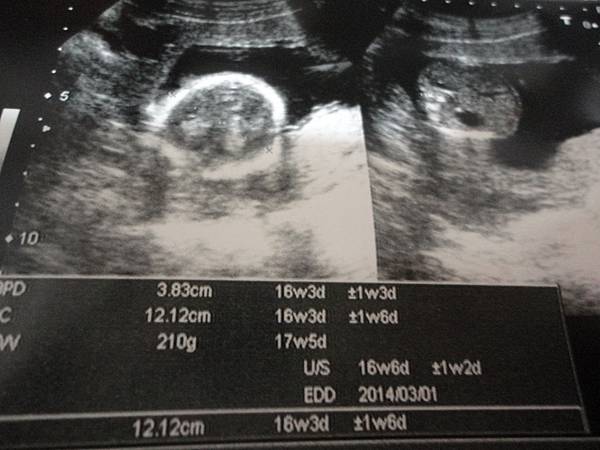

寶寶已經16周多200公克10多公分了

之前11W時拍得比較大張我還至少看得出頭跟身體

下面這張就比較有頭跟身體的FU啦XDDDDDD

那是11周4.8CM時拍的~~